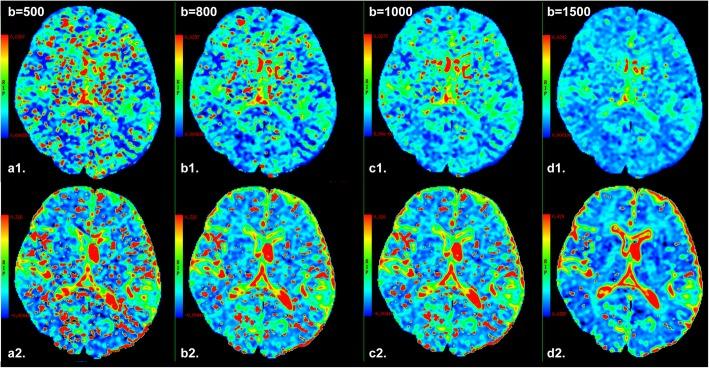

The D* and f value of WM or GM in groups with less low b-values distribution (less than or equal to 5 b-values) were significantly lower than ones in any other group with more low b-values distribution (all P < 0.05), but no significant differences among groups with more low b-values distribution (P > 0.05). In addition, no significant differences in the D, D* and f value of WM or GM were found between group with one and more NEX of low b-values distribution (all P > 0.05). IVIM parameters in normal WM and GM strongly depended on the choice of the high b-value upper limit.

Metrics of IVIM parameters can be affected by low and high b value distribution. Eight low b-values distribution with high b-value upper limit of 800-1000 s/mm may be the relatively proper set when performing brain IVIM studies.